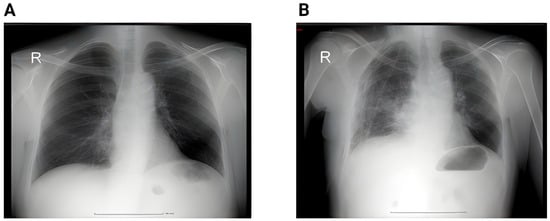

In contrast, the postoperative group demonstrates a clear reduction in both the number and variability of findings, with a lower median and compressed IQR, indicating clinical and radiologic improvement after surgery. Figure 2 shows the proportion of patients and the imaging changes.

Figure 2. (A) Perioperative RX showing a left superior lobe nodule. No pleural effusion, no atelectasis. (B) Second day postoperative x-ray showing hydropneumothorax with significant fluid in the left pleural cavity, and passive atelectasis. (C) 3rd day postoperative showing effective drainage of the fluid with re-expansion infiltrates and juxta-phrenic peak sign. (D) 6 weeks postoperative showing no pleural effusion, no infiltrates.